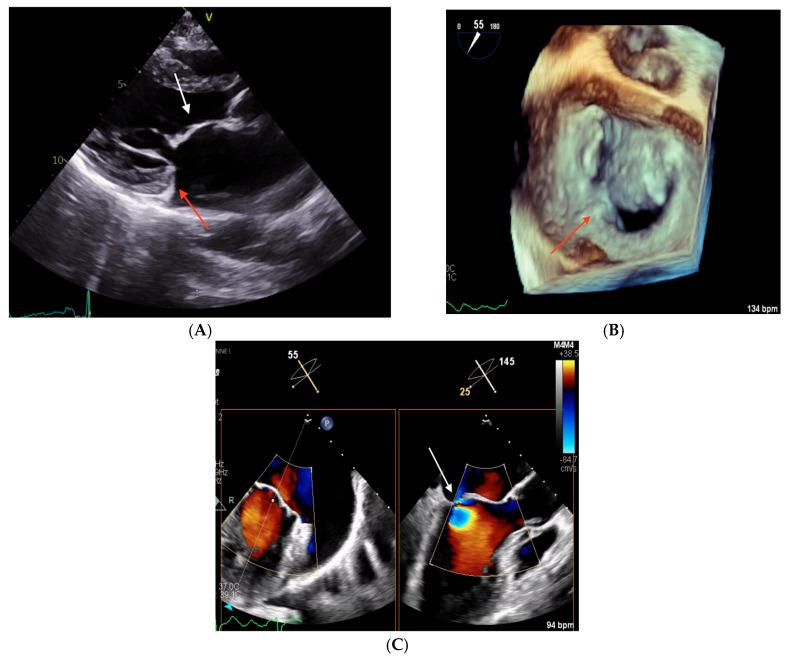

Posterior mitral leaflet hypoplasia is a rare condition, generally diagnosed in children. This paper presents three adult cases of posterior leaflet hypoplasia and comprehensively reviews the existing literature. All patients presented with severe mitral regurgitation necessitating hospitalization. Transthoracic and transesophageal echocardiography were performed to determine the underlying etiology, revealing pronounced posterior mitral leaflet hypoplasia. Each case was evaluated by a multidisciplinary heart team. Surgical mitral valve intervention was feasible in two patients. In one high-risk patient, percutaneous treatment options for MR were explored but ultimately deemed unsuitable due to the anatomical characteristics of the valve. The patient was consequently managed conservatively with medical therapy. These cases demonstrate that posterior mitral leaflet hypoplasia may constitute an underrecognized cause of severe primary mitral regurgitation in adults. The management of such cases can be particularly challenging due to the atypical valvular morphology.

二尖瓣后叶发育不全是一种罕见的病症,通常在儿童期被诊断出来。本文介绍了三例成人二尖瓣后叶发育不全的病例,并对现有文献进行了全面综述。所有患者均因严重二尖瓣反流而需要住院治疗。通过经胸和经食管超声心动图来确定潜在病因,结果显示二尖瓣后叶明显发育不全。每个病例均由多学科心脏团队进行评估。两名患者可行二尖瓣手术干预。在一名高危患者中,探讨了二尖瓣反流的经皮治疗方案,但最终由于瓣膜的解剖特征而认为不合适。因此,该患者接受药物保守治疗。这些病例表明,二尖瓣后叶发育不全可能是成人严重原发性二尖瓣反流的一个未被充分认识的原因。由于瓣膜形态不典型,此类病例的管理可能极具挑战性。